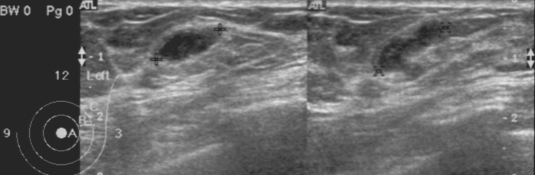

AbstractA case of breast sparganosis was confirmed by surgical excision of a worm (fragmented into 5 pieces) in a 59-year-old Korean woman suffering from a palpable mass in the left breast. Mammography and ultrasonography characteristically revealed the presence of several well-defined, isodense and hypoechoic tubular masses, in the upper quadrant of the left breast, each mass consisting of a continuous cord- or worm-like structure. During surgery, a long segment of an actively moving sparganum of Spirometra sp. and 4 small fragments of the same worm, giving a total length of 20.3 cm, were extracted from the upper outer quadrant of the left breast and the axillary region. The infection source remains unclear, because the patient denied ingesting any snake or frog meat or drinking untreated water. INTRODUCTIONSpargana are the plerocercoid larvae of a pseudophyllidean tapeworm that belongs to the genus Spirometra (Beaver et al., 1984). These larval tapeworms only very rarely grow to the adult stage in the human body (Lee et al., 1984), but the larval stage can cause an infection, namely, human sparganosis (Cho et al., 1974, 1975). Human sparganosis is contracted by eating raw or improperly cooked flesh of snakes or frogs infected with the plerocercoid larvae, by topically applying snake or frog skin to sore eyes, or drinking water contaminated with cyclops harboring the procercoid larvae (Beaver et al., 1984). Human sparganosis cases are reported worldwide, but are more common in Asia, particularly Korea, China, Japan, Taiwan, Vietnam, and Thailand (Beaver et al., 1984). In Korea, 3 human cases were reported for the first time in 1924 (Kobayashi, 1925), but more than 100 cases were subsequently documented before the end of the 1980s in the Republic of Korea (Cho et al., 1975; Min, 1990). The patients were distributed nationwide, although more cases were reported in the northern parts of the Republic of Korea (Min, 1990). Moreover, seroepidemiologic observations in the normal adult population and in epileptic patients revealed high antibody positivities of 1.9% and 2.5%, respectively (Kong et al., 1994). The major reasons why snake meat is consumed in the Republic of Korea are due to the misconception that snake meat is an aphrodisiac, and because it is viewed as field food during military survival training (Cho et al., 1974, 1975; Min, 1990). Radiological (Chung et al., 1995; Kim et al., 2005; Koo et al., 2006) and serological (Kong et al., 1994) techniques can provide useful diagnostic clues of sparganosis. However, in the case of breast sparganosis, radiological images closely resemble those of a neoplasm or granulomatous mastitis (Jeong et al., 1995; Chung et al., 1995; Moreira et al., 1997; Kim et al., 2005). Nevertheless, if a case shows characteristic, though not specific, mammography and ultrasonography findings, these helpfully raise suspicions of breast sparganosis. We encountered an interesting case of breast sparganosis that showed characteristic mammography and ultrasonography findings. The diagnosis was later confirmed by surgical excision of the worm. CASE RECORDA 59-year-old Korean woman, a housewife residing in Seoul, with palpable masses in the left breast of 2 years duration, visited a local clinic, and was suspected as having a soft tissue tumor. She was transferred to a university hospital and then to the Korea Cancer Center Hospital. The patient had a clinical history of hormone replacement therapy some 10 years previously. Except for the palpable breast masses, physical examinations revealed no other abnormalities. She had a good consciousness and nutritive condition, and routine hematological, urinal, and chemical investigations were normal. No active lesion was observed by chest X-ray. Mammography showed multiple, well-defined, isodense, lobular, and continuous cord-like structures in the upper outer quadrant of the left breast (Fig. 1). Ultrasonographic findings also showed well-defined, hypoechoic, tubular masses with folded band-like tracts and a tubule-in-tubule appearance, in the parenchymal layer of the left breast (Fig. 2). A neoplastic disease could not be ruled out, and therefore, fine needle aspiration biopsy was performed on the breast mass, which showed no evidence of neoplastic diseases. Then, breast sparganosis was suspected. For an etiological diagnosis and treatment, left breast tissue was surgically excised. In resected tissue, a lesion with focal fibrosis, without definite mass formation, was observed and histopathologically confirmed as a fibrocystic disease. In the left side of the fibrotic cyst, a long tapeworm segment (Fig. 3), 12.0 cm × 0.7 cm in size, was found across the upper outer quadrant of the left breast toward the axillary region, and carefully extracted. The presence of a scolex was confirmed in this segment. In addition, 4 more fragments of the same worm of 3.3 × 0.8 cm, 1.7 × 0.7 cm, 1.6 × 0.8 cm, and 1.7 × 0.8 cm (Fig. 3), were collected from around the fibrotic cyst. All 5 extracted segments showed active movement, and were fixed in 10% buffered neutral formalin solution for morphological identification. The worm was identified as a sparganum of Spirometra sp., and had a total length of 20.3 cm. The patient denied ingesting snake and frog meat, and drinking untreated water. DISCUSSIONSpargana have the ability to migrate to any part of the human body (Cho et al., 1975; Min, 1990), including the brain (Anders et al., 1984) and oral cavity (Iamaroon et al., 2002). However, predilection sites include the abdomen (38 cases; 28.1%), urogenital organs (30; 22.2%), extremities (24; 17.8%), central nervous system (16; 11.9%), chest (14; 10.4%), and the orbital region (11; 8.1%); based on an analysis of 135 cases reported before 1987 in the Republic of Korea (Min, 1990). Breast sparganosis is rare, i.e., only 2 of these 135 cases (Jung et al., 1981; Nha et al., 1987). However, since 1987, 18 breast cases have been reported (Chi et al., 1988; Choi et al., 1992; Lee et al., 1992; Park and Hwang, 1992; Jeong et al., 1995; Chung et al., 1995; Park et al., 1996; Chang et al., 2000; Sim et al., 2002; Kim et al., 2003). Therefore, the present case becomes the 21st reported case of breast sparganosis in the Republic of Korea; reported cases are briefly summarized in Table 1. Sparganosis cases with fragmented worm segments in tissue, as in the present case, are uncommon, though infections with multiple worms are not uncommon. Seo et al. (1964) reported a case with 3 worms in the left lower scrotal area, where spargana are frequently found. Park et al. (1986) also observed a case with 4 worms in the scrotum and inguinal region. Cho et al. (1975) reviewed 60 sparganosis cases; 44 had only one worm, 6 with 2 worms, 4 with 3 worms, and the remaining 6 had 4-12 worms. However, in cases of breast sparganosis, only 1 worm has been reported in most patients (Table 1). In our case, 5 worm segments were recovered from the upper quadrant of the left breast and axillary region. All of these segments were actively motile after excision, and thus initially we believed that there were 5 distinct worms. However, careful observation confirmed them to be worm segments from a single worm, the longest of which was equipped with the scolex and neck portion (Fig. 3). With regard to the source of infection, Min (1990) summarized the past histories of sparganosis patients and noted that the majority of patients had experience of eating various kinds of animal fleshes including snakes and frogs, and that some of the patients had drank untreated water. Moreover, although the likelihood of drinking untreated water is probably similar for men and women, the eating of snakes or frogs is likely to be far more common in men, which concurs with a known disease gender preference, i.e., men, 94 of 119 cases, and women, 25 of 119 cases (Min, 1990). With regard to breast sparganosis, patients reported in the Republic of Korea to date have all been females. Moreover, the majority have denied eating snake or frog meat, which leaves the source of infection in these cases obscure (Table 1). Also in the present case, the mode of infection was unclear, since the patient denied eating any snake or frog meat or drinking untreated water. Thus, the source of sparganum infection in female patients without a history of exposure to known sources should be clarified. Breast sparganosis presents as soft tissue nodules, as in the present case, and is confused with neoplastic masses in radiological images (Chuen-Fung and Alagaratnam, 1991; Jeong et al., 1995). For example, its mammographic features are usually multiple, lobular, marginated, amorphic, and solid masses without calcifications, which are similar to the features of the circumscribed breast cancer or benign tumor-like fibroadenoma (Chung et al., 1995; Kim et al., 2005). Thus, a confirmatory diagnosis should be established by extracting the worm responsible or by examining surgical pathology specimens. However, as shown in the present case, mammography findings can be characteristic and highly useful for a pre-operative diagnosis of breast sparganosis. Ultrasonographic findings may also be useful for the pre-operative diagnosis of breast or other organ sparganosis (Chung et al, 1995; Cho et al., 2000; Kim et al., 2005). In breast sparganosis, elongated, folded, band- or tunnel-like hypoechoic tubular structures in heterogenous, hyperechoic masses are characteristic (Chung et al., 1995), whereas in subcutaneous and musculoskeletal sparganosis, serpiginous, cystic, tubular tracts, with internal anechogenicity and posterior echo enhancement, are important characteristics (Cho et al., 2000). Intraluminal lesions formed by the larvae or debris and peritubular echo changes produced by chronic inflammatory reactions have been noted in a half of musculoskeletal sparganosis cases (Cho et al., 2000). However, findings of elongated, serpiginous, and tubular structures may also be obtained in other types of diseases, such as, ectatic ducts, radiation edema, superficial thrombophlebitis, and congestive heart failure (Chung et al, 1995; Kim et al., 2005). Nevertheless, such findings together with high antibody titers against sparganum, and characteristic mammography and ultrasonography findings will be very useful for a pre-operative diagnosis of sparganosis. REFERENCES1. Anders K, Foley K, Stern WE, Brown WJ. Intracranial sparganosis: an uncommon infection. J Neurosurg. 1984. 60:1282-1286.      2. Beaver PC, Jung RC, Cupp EW. Clinical Parasitology. 1984. 9th ed. Philadelphia, U.S.A.: Lea & Febiger; 499-504. 3. Chang YK, Kim KC, Cho HJ. Sparganosis in the female breast. J Korean Surg Soc. 2000. 58:285-287 (in Korean). 5. Cho JH, Lee KB, Yong TS, Kim BS, Park HB, Ryu KN, Park JM, Lee SY, Suh JS. Subcutaneous and musculoskeletal sparganosis: imaging characteristics and pathologic correlation. Skeletal Radiol. 2000. 29:402-408.      6. Cho SY, Ahn GH, Ro JY, Hahn JH. Two cases of sparganosis caused by survival training in army. J Korean Med Ass. 1974. 17:367-371 (in Korean). 7. Cho SY, Bae JH, Seo BS. Some aspects of human sparganosis in Korea. Kisaengchunghak Chapchi. 1975. 13:60-77.      8. Choi YH, Oh HJ, Jeong YK, Lee SC. A case of multiple spargana in female breast. J Korean Surg Soc. 1992. 43:300-304 (in Korean). 10. Chung SY, Park KS, Lee Y, Park CK. Breast sparganosis: mammographic and ultrasound features. J Clin Ultrasound. 1995. 23:447-451.      11. Iamaroon A, Sukontason K, Sukontason K. Sparganosis: a rare case of the oral cavity. J Oral Pathol Med. 2002. 31:558-560.      12. Jeong JK, Ryu BY, Lee HW, Kim HK, Choi CS. Sparganosis of the breast. J Korean Surg Soc. 1995. 48:428-432 (in Korean). 13. Jung PJ, Yoo BO, Park CY, Koo BH. A case of human sparganosis in the breast. J Korean Surg Soc. 1981. 23:269-271 (in Korean). 14. Kim HS, Cha ES, Kim HH, Yoo JY. Spectrum of sonographic findings in superficial breast masses. J Ultrasound Med. 2005. 24:663-680.    15. Kim YS, Hwang MS, Lee JK, Kim DS, Lee SK. US findings of breast sparganosis. J Korean Soc Med Ultrasound. 2003. 22:151-156 (in Korean). 16. Kobayshi H. On the animal parasites in Korea. Japan Med World. 1925. 5:9-16 (in Japanese). 17. Kong Y, Cho SY, Kang WS. Sparganum infections in normal adult population and epileptic patients in Korea: a seroepidemiologic observation. Korean J Parasitol. 1994. 32:85-92.     18. Koo JH, Cho WH, Kim HT, Lee SM, Chung BS, Joo CY. A case of sparganosis mimicking a varicose vein. Korean J Parasitol. 2006. 44:91-94.        19. Lee BJ, Ahn SK, Kim SC, Lee SH. Clinical and histopathologic study of sparganosis. Korean J Dermatol. 1992. 30:168-174 (in Korean). 20. Lee SH, Chai JY, Seo BS, Cho SY. Two cases of human infection by adult of Spirometra erinacei. Korean J Parasitol. 1984. 22:66-71.     22. Moreira MA, de Freitas Jr. R, Gerais BB. Granulomatous mastitis caused by sparganum. A case report.. Acta Cytol. 1997. 41:859-862.    23. Nha SG, Cho WH, Lim TJ, Park YK. A case of sparganosis in female breast. J Korean Surg Soc. 1987. 32:473-475 (in Korean). 24. Park CK, Hwang WC. Sparganosis of the breast: a case report. Human Sci. 1992. 16:327-330 (in Korean). 25. Park JM, Hwang JC, Choi YB. Sparganosis of the breast. J Korean Radiol Soc. 1996. 34:843-845 (in Korean). 26. Park JY, Choi YS, Yeum KY, Ahn DH. A case of sparganosis infecting on the scrotum and inguinal area. J Koryo General Hosp. 1986. 9:185-187 (in Korean). Fig. 1Mammogram of the present breast sparganosis case. A: Mediolateral oblique view, B: Craniocaudal view. Welldefined, isodense, lobular, and continuous cord-like structures (arrows) were characteristically observed in the upper outer quadrant of the left breast.   Fig. 2Ultrasonograms of the present sparganosis case, showing a well-defined hypoechoic, tubular mass with internal heterogeneous echogenicity, and tubule-in-tubule appearance in the subcutaneous layer of the upper outer quadrant of the left breast.   Fig. 3Segments of the sparganum obtained by surgical removal. A long segment with a scolex (arrow) was extracted across the left breast to the axillary region. The other 4 segments were collected from lumps in the same left breast.   Table 1.Breast sparganosis cases reported in the Republic of Korea